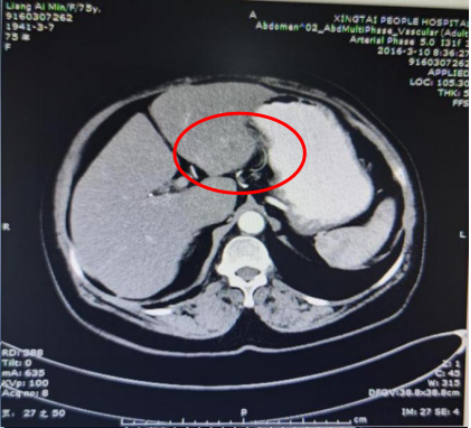

基本信息:性别 女,年龄 78岁,身高 159cm,体重 62kg。 主诉:结肠癌及肝转移瘤术后2年6个月(首次就诊时间为2018-09-10)。 既往史、个人史:“2型糖尿病”20年,予“二甲双胍 0.5g 口服 2次/日、门冬胰岛素注射液皮下注射,早 30U,晚 28U;甘精胰岛素皮下注射 20U ”降糖治疗,血糖控制一般。 家族史:无特殊。 02 初诊病史 体格检查、B超、CT及其他辅助检查。 体表面积1.60m,体格检查:浅表淋巴结未及肿大,双肺呼吸音粗,未闻及干湿性啰音,心律规整,未闻及杂音,腹壁可见陈旧性手术瘢痕,愈合良好,腹软,未及肿物,无压痛,肛查-,双下肢无水肿,起病隐匿,体检行腹部超声发现肝脏占位。 肠镜(2016-3-12):乙状结肠肿物。 咬检病理:(乙状结肠)腺癌。 肝胆胰增强CT(2016-3-10):肝左叶占位。 考虑:乙状结肠癌Ⅳ期 肝转移。 2016-3-21 于外院行“乙状结肠癌根治术+肝左叶转移瘤切除术”,术中予输血治疗,术后恢复慢,切口延期愈合。 术后病理:结肠中分化腺癌伴坏死形成,大者3.5cm×3.2cm×0.5cm,癌组织侵及浆膜脂肪层,脉管内癌栓形成,小者1cm×1cm×0.5cm,癌组织侵及粘膜下层。肠壁周围淋巴结癌转移(3/6),T3N1M1。(肝左叶)肝脏转移性腺癌伴大片坏死形成,大小6.6cm×6cm×4.5cm,结肠来源,残端及吻合口上下缘肠壁未见肿瘤侵及。 基因检测:KRAS、NRAS、BRAF 均未见突变。 初步诊断:乙状结肠癌Ⅳ期(pT3N1M1),同时性肝转移,中分化腺癌,2型糖尿病。 03 治疗方案 2016-4 XELOX 方案化疗1周期(具体剂量不详)因不良反应较重,未完成术后辅助治疗疗程。未予后续治疗,定期复查,病情稳定 胸腹CT(2017-3-19 ):右肺下叶新结节,考虑转移;肝左外叶转移瘤切除术后改变。 2017-4-1 于外院行局部肺肿物射频消融术,无治疗反应,恢复良好。 胸CT(2017-12-5):肺部新发结节,考虑转移。 【一线治疗方案(2017-12至2018-9)】 卡培他滨 1.5g po d1-14 q3w,共10个周期。 不良反应:1度消化道反应。 期间疗效评价:SD。 胸腹增强CT(2018-9-11):符合结肠癌切除术后,肝左叶切除后改变,双肺多发结节,部分较前增大。 2017-12-5 2018-9-11 建议调整方案治疗,患者家属拒绝,继续口服卡培他滨至2019年3月。 疗效评估: ECOG PS评分1分,新发活动后胸闷、气短症状 胸腹平扫CT(2019-3-26):双肺多发结节,较前增大;肝左外叶转移瘤切除术后改变。 2018-9-11 2019-3-26 评估PD。 【二线治疗方案(2019-4至2020-5)】 贝伐珠单抗 300mg ivgtt d0(体重62kg); 卡培他滨 1.5g po d1-14 q3w,共15周期。 不良反应:1级高血压、1度消化道反应。 疗效评估: 胸腹CT(2020-5-21):符合结肠癌术后、肝左叶切除术后,肝左切缘旁异常密度灶,左髂总动脉旁淋巴结;双肺多发结节,部分较前增大,右肺门肿物较前增大。 疗效评价:PD。 【三线治疗方案(2020-5至2020-10)】 西妥昔单抗 600mg ivgtt d0(体表面积1.66 m2); 亚叶酸钙 500mg ivgtt d1; 氟尿嘧啶 500mg ivgtt ,随后3500mg iv泵入 q2w,共9周期。 不良反应:无皮疹、腹泻、恶心、呕吐等。 疗效评估: 胸腹平扫CT(2020-09-07):右肺下叶背段软组织肿块,较前略减小,双肺多发小结节,转移瘤,同前;结肠癌术后、肝左叶切除术后改变,肝左切缘旁异常密度灶同前相仿,腹膜后左侧髂总动脉旁淋巴结同前。 2020-7-23 2020-9-7 疗效评价:SD(缩小趋势)。 胸腹平扫CT(2020-10-24):右肺下叶背段软组织肿块,较前(2020-9-7)略减小,双肺多发小结节,转移瘤,部分较前减小,结肠癌术后、肝左叶切除术后改变,肝左切缘旁异常密度灶同前相仿,腹膜后左侧髂总动脉旁淋巴结同前。 2020-9-7 2020-10-24 疗效评价:SD(缩小趋势)。 胸腹平扫CT(2020-12-13):右肺下叶背段软组织肿块,较前(2020-10-24)未见著变,双肺多发小结节,转移瘤,较前未见著变,结肠癌术后、肝左叶切除术后改变,肝左切缘旁异常密度灶同前相仿,腹膜后左侧髂总动脉旁淋巴结同前。 2020-12-13 疗效评价:SD。 患者未规律返院行西妥昔单抗维持治疗。 胸腹增强CT(2021-1-5):右肺下叶背段软组织肿块,较前(2020-12-13)增大,双肺多发小结节,转移瘤,左肺尖结节较前增大,余未见著变,左侧髂总动脉旁淋巴结较前增大。 疗效评价:PD。 【四线治疗方案(2021-1至2021-10)】 安罗替尼 8mg po 1次/日 d1-14 (2021-3 起因高血压2级,药物控制不佳调整为8mg qod ); 卡培他滨 1g po 2次/日 d1-14 q3w (2021-4 起因乏力2级不能耐受停服)。 不良反应:2级高血压,2级乏力,1级胆红素升高,1度消化道反应。 疗效评估: 胸腹增强CT(2021-10-3):右肺下叶背段占位,考虑恶性肿瘤,较前增大,双肺多发转移瘤,部分较前略增大,结肠癌术后、直肠区肠管明显扩张,肝左叶切除术后改变,切缘旁占位伴肝内胆管扩张,累及胆总管,考虑恶性病变,较前增大,腹膜后左侧髂总动脉旁淋巴结,较前增大,累及左侧输尿管伴以上输尿管及肾盂扩张。 2021-10-3 疗效评价:PD。 疗效评估: 胸腹增强CT(2021-10-3):右肺下叶背段占位,考虑恶性肿瘤,较前增大,双肺多发转移瘤,部分较前略增大,结肠癌术后、直肠区肠管明显扩张,肝左叶切除术后改变,切缘旁占位伴肝内胆管扩张,累及胆总管,考虑恶性病变,较前增大,腹膜后左侧髂总动脉旁淋巴结,较前增大,累及左侧输尿管伴以上输尿管及肾盂扩张。 【后线治疗方案(2021-10至2021-11)】 曲氟尿苷替匹嘧啶片(TAS-102) 40mg po 2次/日 d1-5,d8-12,q4w; 贝伐珠单抗 200mg ivgtt q2w。 不良反应:无皮疹、腹泻、恶心、呕吐等。 疗效评估: 胸腹增强CT(2021-11-17):右肺下叶背段占位,较前变化不明显,双肺多发转移瘤,较前变化不明显,结肠癌术后、直肠区肠管明显扩张,肝左叶切除术后改变,切缘旁占位伴肝内胆管扩张,累及胆总管,考虑恶性病变,较前变化不明显,腹膜后左侧髂总动脉旁淋巴结,较前减小,肾盂扩张较前减轻。 疗效评价:SD。 胸腹增强CT(2021-11-17):右肺下叶背段占位,较前变化不明显,双肺多发转移瘤,较前变化不明显,结肠癌术后、直肠区肠管明显扩张,肝左叶切除术后改变,切缘旁占位伴肝内胆管扩张,累及胆总管,考虑恶性病变,较前变化不明显,腹膜后左侧髂总动脉旁淋巴结,较前减小,肾盂扩张较前减轻。 04 病例小结 患者为高龄女性,诊断为直肠癌Ⅳ期多发转移,KRAS、NRAS、BRAF 均未见突变。 OS为69个月。